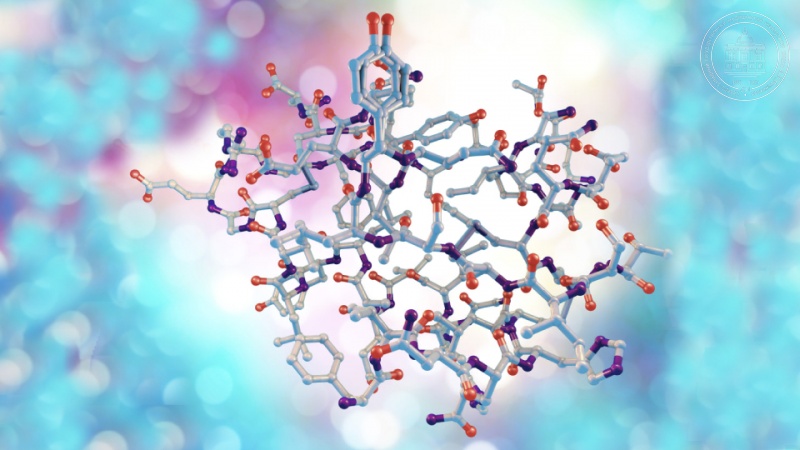

Фотографии медицинских исследований инсулиномы и синдрома Триады Уиппла